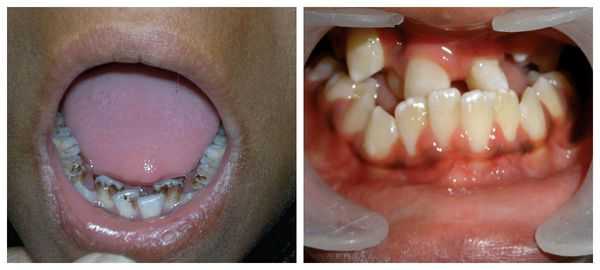

Перечисленные лицевые аномалии могут сопровождаться нарушением слуха, неправильной закладкой и прорезыванием зубов и другими нарушениями, которые могут повлиять на психофизическое развитие ребёнка.

В целом расщелины лица и/или нёба, недоразвитие верхней и нижней челюсти, лицевых мышц, скуловой и/или височной костей способны вызывать проблемы с зубами, трудности при кормлении, нарушение речи и изменение эстетических параметров лица.

При рентгенологическом исследовании черепа определяется брахицефалия: мозговой череп увеличен в поперечнике и уменьшен в передне-заднем размере. Основание черепа укорочено в поперечном направлении и несколько удлинено в продольном. Кости свода, особенно лобная, истончены и как бы раздуты, значительно выдаваясь в стороны. Передний родничок остается незаращенным. В местах перекреста швов могут наблюдаться и дополнительные роднички или дополнительные костные включения в самих швах. Кости лицевого черепа малы, верхнечелюстные пазухи недоразвиты. Размеры нижней челюсти не изменены. Обнаруживаются аномалии прикуса, расположения, формы и сроков прорезывания зубов.